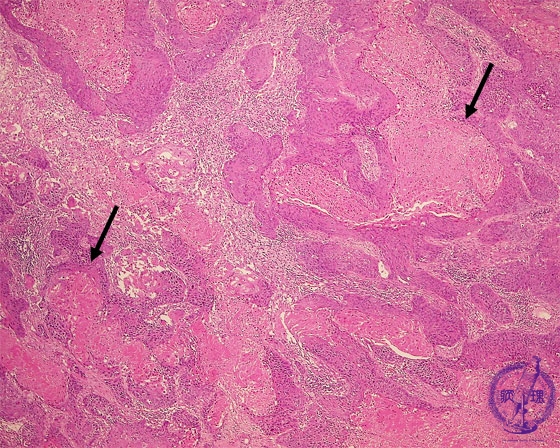

- ★(17)Non-small cell lung carcinoma(squamous cell carcinoma)

Microscopic view (HE stain, low power view): Squamous cell carcinoma proliferates in an irregular geographic (map-like) pattern. Keratinocyte necrosis is prominent (arrow). Unlike in adenocarcinoma well-formed tubules are not seen.